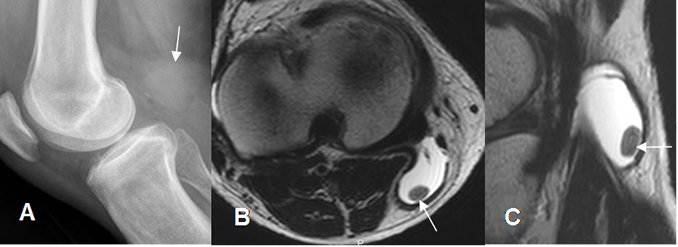

Fig 179. Quiste de Baker complicado.

A: Rx lateral de rodilla. Prominencia de los tejidos blandos en la región poplítea, por la presencia de quiste de Baker.

B: RM axial en T2 y C: RM sagital en T2. Dentro del quiste de baker, se identifica cuerpo libre no calcificado.